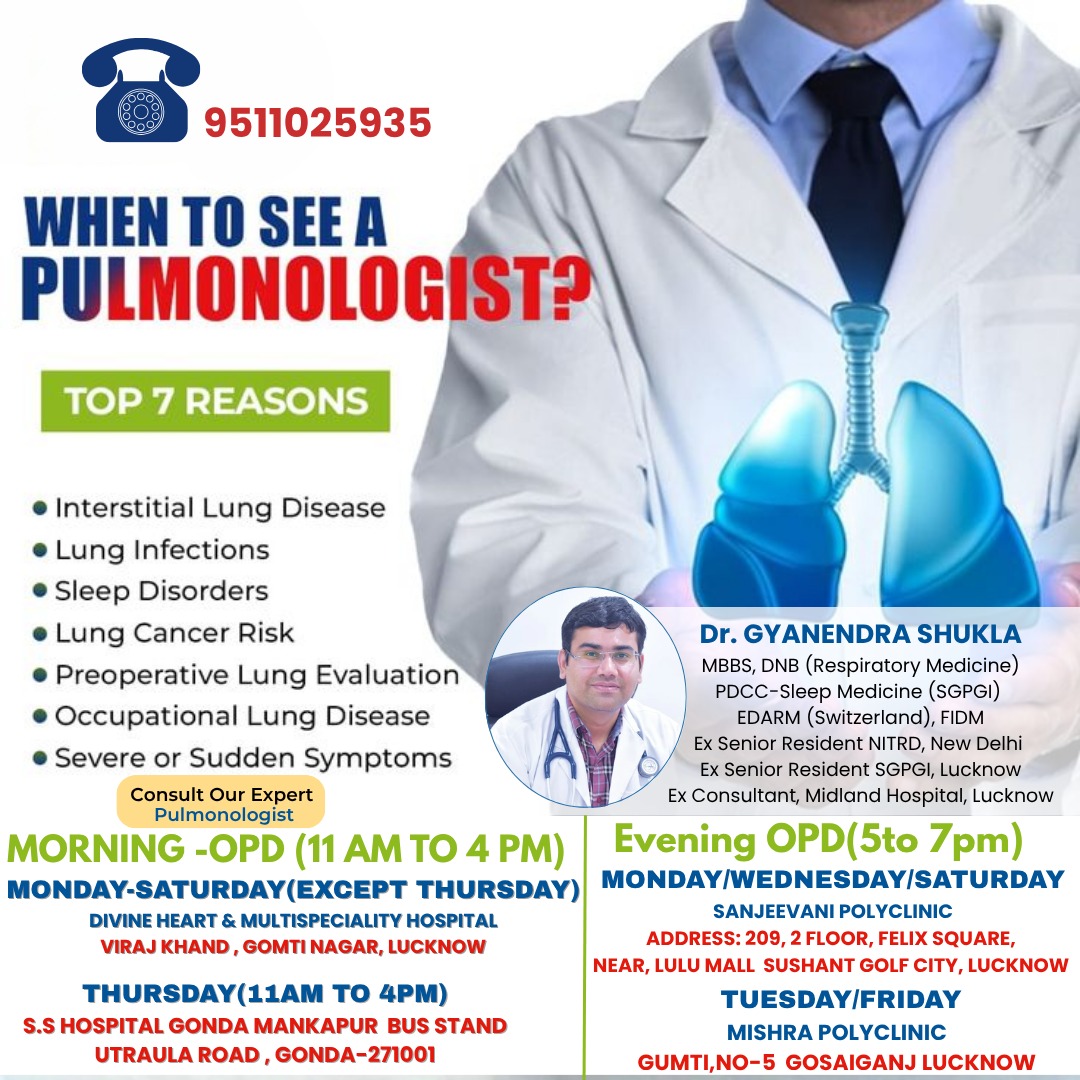

Dr. Gyanendra Shukla

M.B.B.S., DNB (Respiratory Medicine), PDCC-Sleep Medicine (SGPGI), EDARM (Switzerland), FIDM

Ex Senior Resident NITRD, New Delhi,

Ex Senior Resident SGPGI, Lucknow,

Ex Consultant, Midland Hospital, Lucknow.

Specialist in Tuberculosis, Asthma, COPD, ILD, Pneumonia, Allergy, Bronchoscopy, Chest Diseases, Critical Care, and Sleep Disorders.

Dr. Gyanendra Shukla is a distinguished medical professional with a stellar academic background and significant expertise in pulmonary medicine. He obtained his MBBS degree from the esteemed Madurai Medical College, followed by post-graduation in respiratory medicine from the prestigious National Institute of Tuberculosis and Respiratory Diseases in New Delhi.